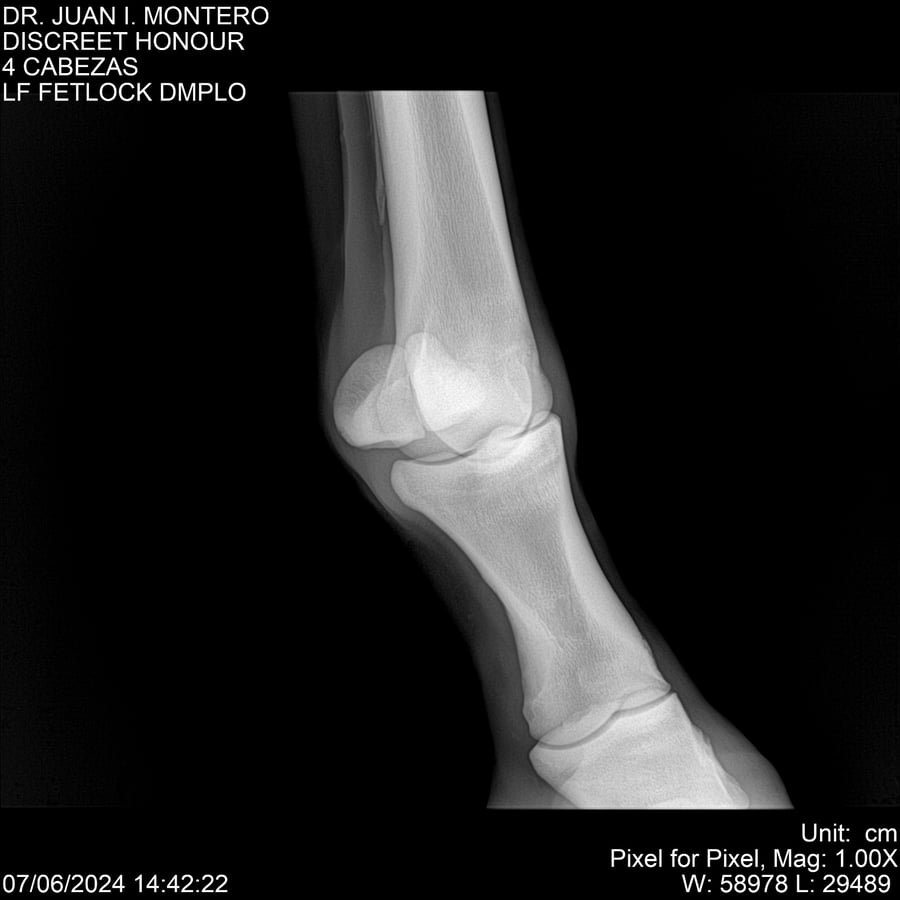

LOTE 6, DISCREET HONOUR 🔥 🔥 🔥 Lote Anterior Volver al remate Lote Siguiente Ficha Contacto Montevideo - Ficha del Lote Identificador: #281093 Categoría: Yeguarizos Montevideo - 82 Visualizaciones ClicData Contacto Empresa: Abelenda N. R., Walter Hugo Nombre*: Teléfono* : E-mail* : Mensaje Enviar Registrese gratis Este contenido Exclusivo está disponible sólo para usuarios registrados Ingresar